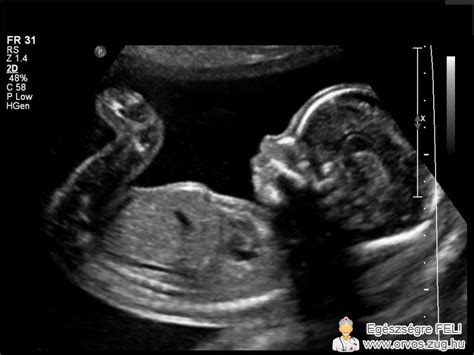

Az üres petezsák akkor alakul ki, ha ugyan a megtermékenyített petezsák megtapad a méhfalon, de az embrió kb. a hatodik hét után nem fejlődik tovább. A petezsák az, ami körülveszi az embriót és a magzatvizet, és a magzat táplálását, fejlődését segíti. Ez általában az ötödik hét körül már látható, ezt követően pedig nagyjából egy mm az átlagos növekedése naponta. A petezsák lehet kóros alakú vagy üres még az után is, hogy a szikhólyagnak láthatónak kellene lennie.

Az ultrahangos vizsgálat során az orvos egy sötét foltot lát a méhben, amely a petezsák, de hiányzik belőle a szikhólyag vagy az embriócsomó. Ez a diagnózis általában a 6. és 7. terhességi hét környékén válik biztossá, amikor már látszódnia kellene a szívműködésnek. Az orvosok gyakran néznek sorozatos béta-HCG szintet is a vérből, hogy lássák a trendet. Fontos tudni, hogy a méh helyzete - például a hátrahajló méh - vagy a kismama hasfali zsírszövete is nehezítheti az ultrahangos láthatóságot a korai hetekben. Sokan teszik fel a kérdés: miért történik ez meg? Az üres petezsák és a kémiai terhesség hátterében szinte mindig genetikai hiba áll, amit a mindennapi stressz nem befolyásol.